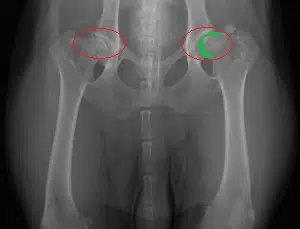

To give you an idea on what happens to your Rottweiler’s body when it develops canine hip dysplasia, let’s familiarize ourselves with what a normal and healthy hip joint looks like.

Circled in yellow are what a dog’s hip joints should normally look like. See how the ball of the leg bones are rounded and fits the shape of the hip socket almost perfectly.

While the green highlight, it traces the shape of the ball of the bone and notices how it’s not perfectly rounded anymore. Some areas seem to have rubbed off.